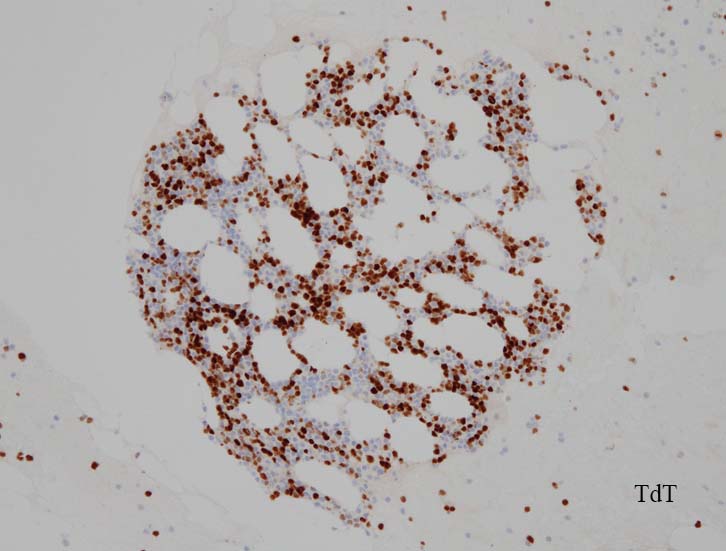

blastic cellsは, CD45+, CD34+, CD38+, TdT+, CD7+, HLA-DR+, CD123+. cCD3-, sCD3-(FCM), CD20-, CD19-とCD79a-(?) (plasma cellが陽性でIHCでは判定が難しい), MPO-.

AULはcCD3、MPO、CD19、cCD22、およびCD79a発現を欠き, 通常1つの表面系統マーカー( CD13、CD33、またはCD7など)のみを発現する.CD38またはTdT発現を伴って, CD34およびHLA-DRが陽性になる. *2

この論文では AULとAML-M0の違いは, AULにおいてPHF6変異が多いこと, 芽球にTdTが発現する率が高いこととされている.